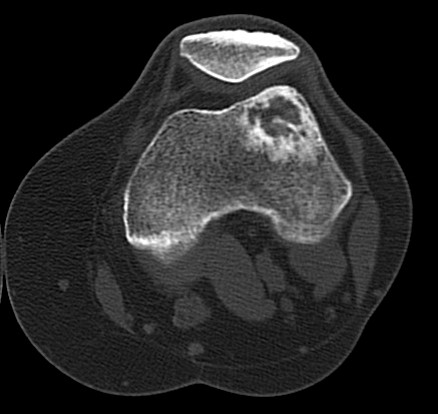

Fig. 3: CT Scan of the left knee showing a lytic lesion within the lateral supracondylar femur with surrounding sclerosis. No definite osseous or cartilaginous matrix was seen.